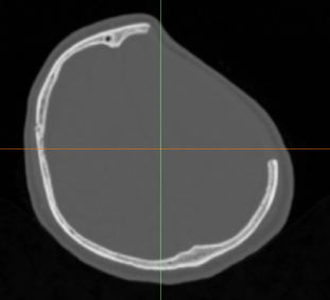

術(shù)前診斷:左側(cè)額顳部顱骨缺損

左側(cè)額顳部顱骨缺損